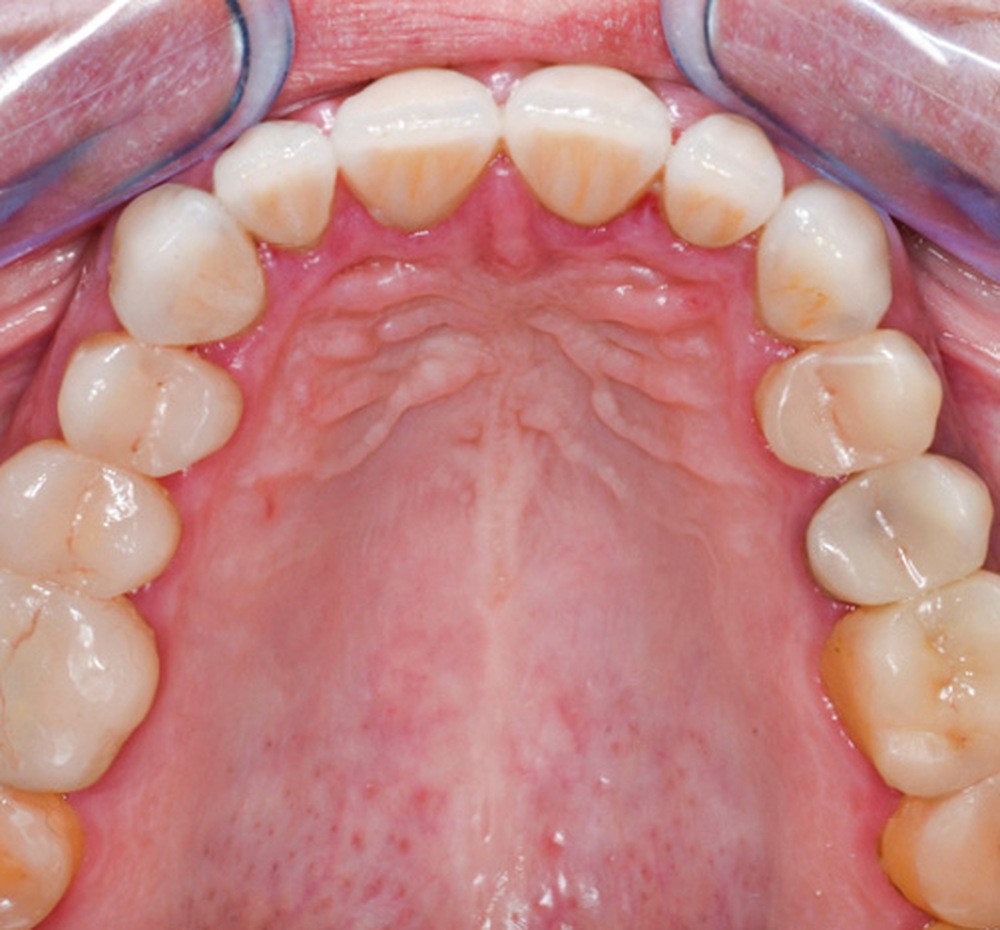

Mme V. est adressée au cabinet dentaire pour une réhabilitation de son sourire. À l’examen clinique, elle présente des usures sur l’ensemble de son maxillaire (fig. 17 et 18). Après évaluation du décalage OIM-ORC, une position de référence en relation centrée avec une dimension verticale augmentée est enregistrée. Pour valider cette position, il est demandé au laboratoire de réaliser un wax-up virtuel. Ce dernier est validé puis transféré en bouche pour essayage (fig. 19 et 20).

Ce mock-up est équilibré puis transformé en projet provisoire pour trois mois afin de s’assurer de la stabilité, du confort masticatoire et de l’esthétique. Au terme de ces trois mois, une empreinte de la situation est réalisée ainsi que l’enregistrement de l’occlusion ; enfin les secteurs postérieurs sont préparés pour recevoir des overlays. L’ensemble des informations (position et forme) est repris au sein du laboratoire pour dessiner les prothèses d’usage. Ces dernières seront produites par usinage, puis maquillées avant d’être envoyées au cabinet pour assemblage par collage sous champ opératoire (fig. 21 à 23).

Une fois les secteurs postérieurs et l’assise occlusale rétablis, le bloc incisivo-canin antérieur est préparé pour des restaurations adhésives. Là encore, l’assemblage se fait par collage sous champ opératoire. Le suivi est assuré pour contrôler la pérennité du traitement et une éventuelle reprise des usures. Pour ce faire, des rendez-vous cliniques avec réalisation d’une empreinte optique semestrielle sont programmés. La précision de l’empreinte permet ainsi de dépister le moindre phénomène d’usure (fig. 24 à 27).